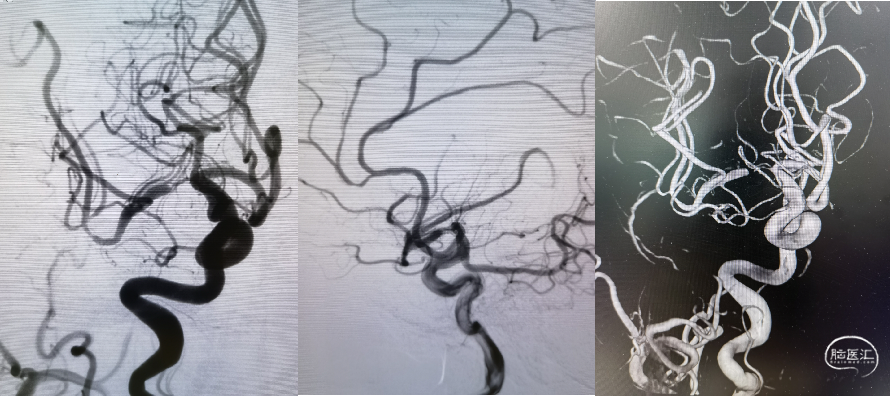

DSA提示:右侧大脑中动脉M1起始部极重度狭窄、次全闭塞,狭窄远端M1段管径约2.1mm,近端颈内动脉末端管径约3.3mm;M2段主干中度狭窄,分水岭下移;颈内动脉入路非常迂曲。

借助支架输送系统回送支架导管至支架尾端顶住再撤出支架系统,保留微导丝,观察20分钟,见血流通畅,撤出微导丝,回撤导引导管和中间导管,正侧位减影和非减影像造影提示大脑中动脉血流通畅良好,支架远近端均匀贴壁,分水岭恢复正常。